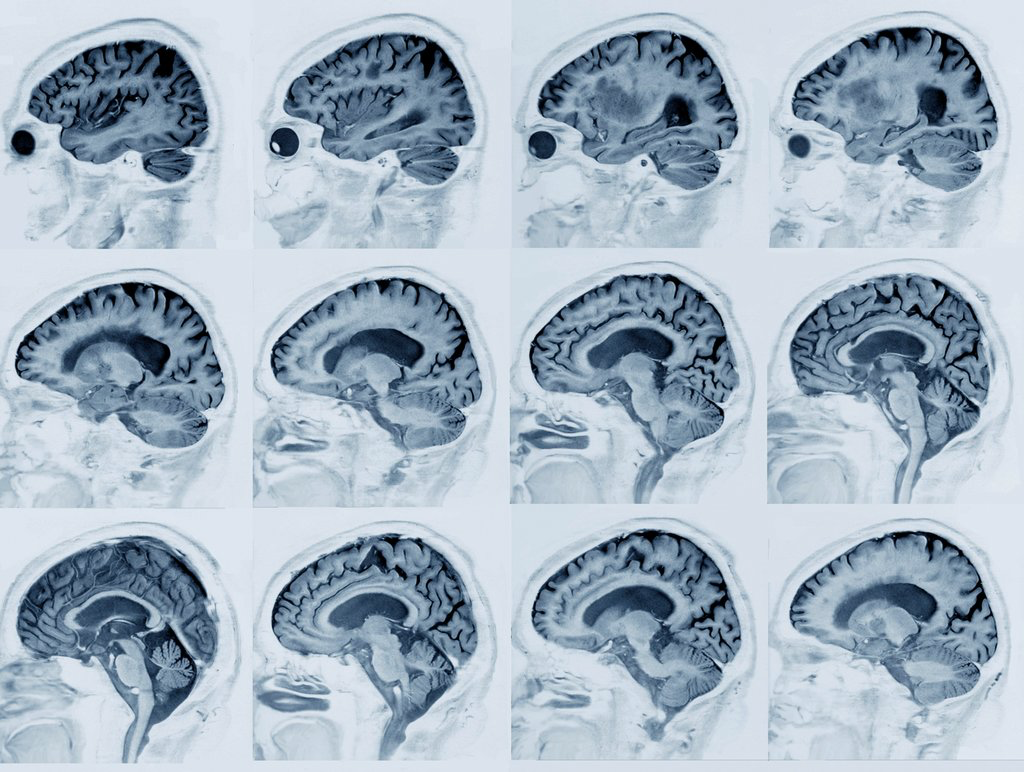

Image showing the various levels of plaque accumulation of beta amyloid within brains. Alzheimer’s patients have particularly high, progressing levels of accumulation believed to contribute to loss of function. Image courtesy of Zephyr/Science Source